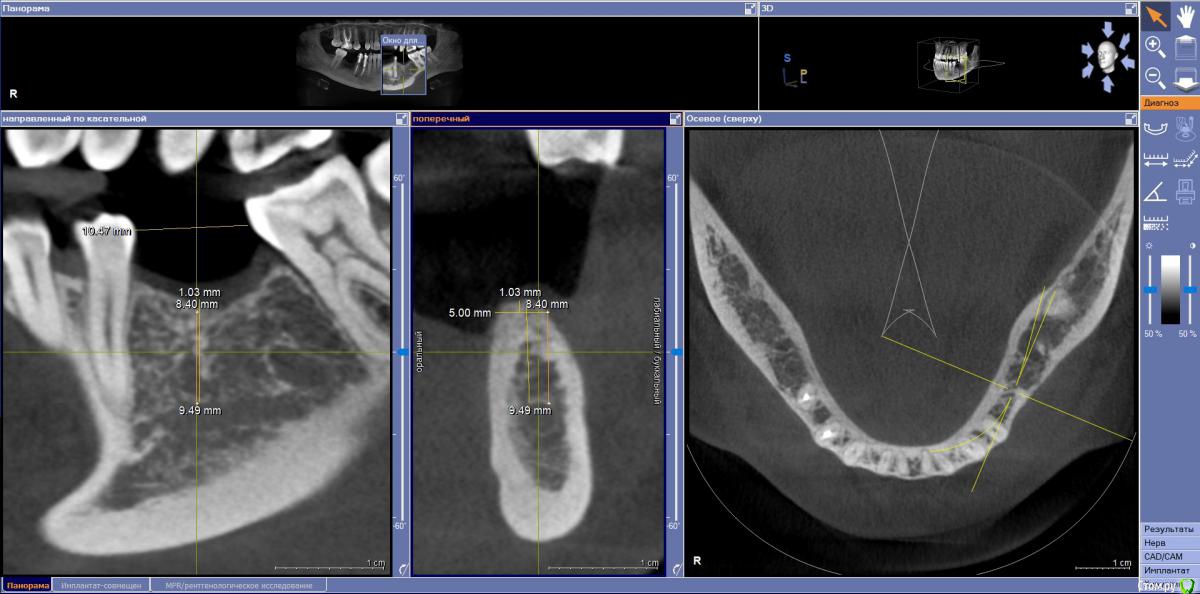

Fin Опубликовано 29 июля, 2020 Поделиться Опубликовано 29 июля, 2020 Здравствуйте коллеги. У пациента отсутствуют зуб 3.5 и 3.6. и высоко расположенный канал тройничного нерва. Что бы вы сделали в данном случае? Наращивать ширину? Ставить ССТ? Ссылка на комментарий

annda Опубликовано 3 августа, 2020 Поделиться Опубликовано 3 августа, 2020 (изменено) Стоял до этих имплантатов суперлайн коротыш 7мм,одиночка.Заколебались с раскруткой винта,ходила каждый месяц.Плюнула,решили выкрутить,переставить на эти.КТ после удаления. Изменено 3 августа, 2020 пользователем annda 1 Ссылка на комментарий

annda Опубликовано 4 августа, 2020 Поделиться Опубликовано 4 августа, 2020 Что-то с загрузкой пошло не так,извините.Контроль после постановки и контроль с абатментами(через 3 месяца) Ссылка на комментарий